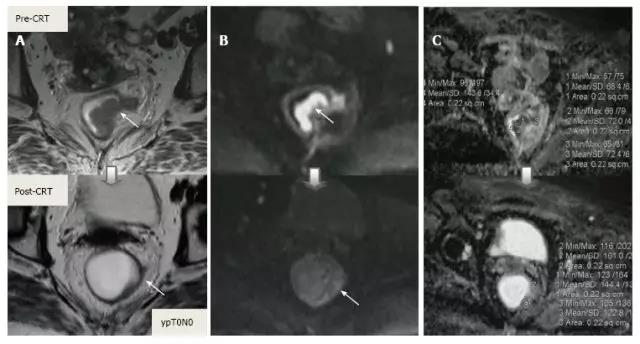

除了形态学发现之外,DWI 可以提供与细胞水平相关的功能信息变化。CRT 后细胞密度减低、纤维化或坏死使弥散加强,从而降低弥散加强图像的弥散信号强度,并增加在 ADC 图像 [ADC 值和 ADC 的信号强度(图 18 和图 19)。

虽然 DWI 能从纤维化中区分活的肿瘤细胞,也能区分治疗反应好与差,但不能预测完全缓解(图 20)。而且 CRT 后不能使用 DWI 评估肿瘤反应,因为即便在治疗前此类肿瘤也显示为 ADC 高密度(图 21)。

图 19. DWI 对放化疗后 ypT0 直肠肿瘤重新分期。A. 治疗后 T2 加权轴位图像显示,先前直肠肿瘤区域的低信号强度纤维化厚壁(箭头),难以确定该区域是否含有肿瘤细胞还是完全缓解;B. 在治疗后 DW 图像(B-800)中,在以前的肿瘤区域(箭头)没有弥散信号,与完全缓解相符。在这种情况下,DWI 正确区分肿瘤与纤维化;C. ADC 图像显示治疗后平均 ADC 增加(0.70 × 10-3 mm²/s 对比 1.40 × 10-3 mm²/s)与治疗反应相符,但不能预测完全缓解。

图 20. DWI 对放化疗后 ypT0 直肠肿瘤重新分期。A. T2 加权轴位图像显示低信号强度纤维化的厚壁,可疑残留肿瘤区域具有中等信号强度(长箭头);B. 治疗后 DWI 图像,低信号强度的小焦点与残留肿瘤(长箭头)相符;C. ADC 图像显示治疗后平均 ADC 增加,与治疗反应相符, 但没有完全缓解。可疑直肠淋巴结(箭头)在 CRT 后 T2 和 DWI 不可见,但另外两个仍然可见(短箭头)。此例是 DWI 评估肿瘤和淋巴结反应假阳性。